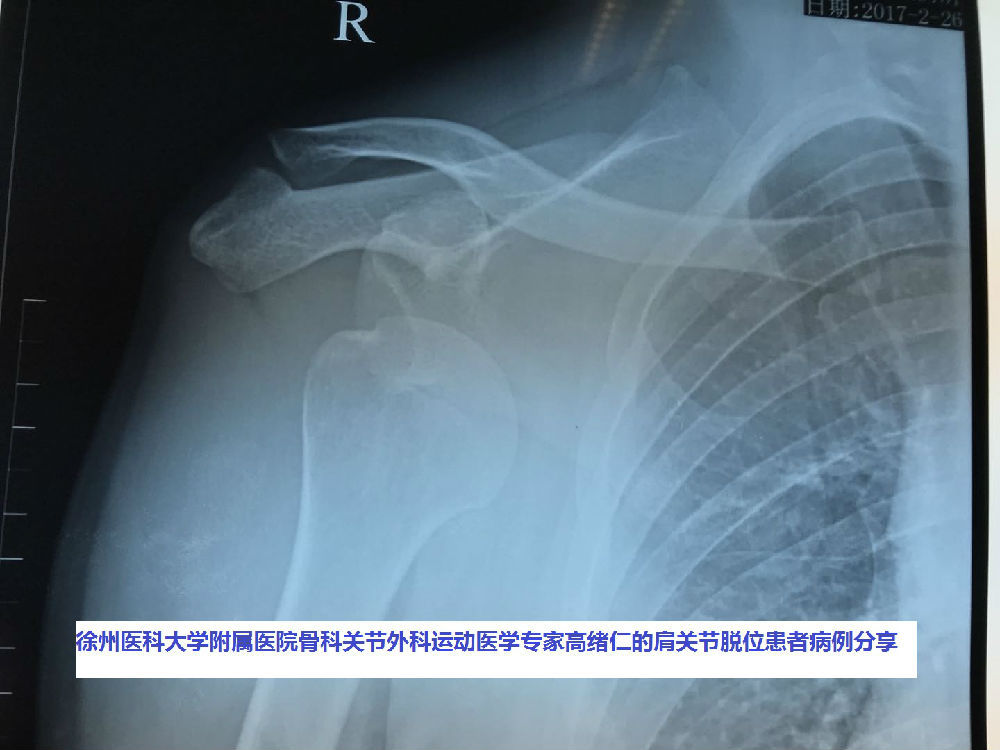

肩关节脱位合并大结节骨折术后翻修病人1例

肩膀脱臼图片

肩膀脱臼x光